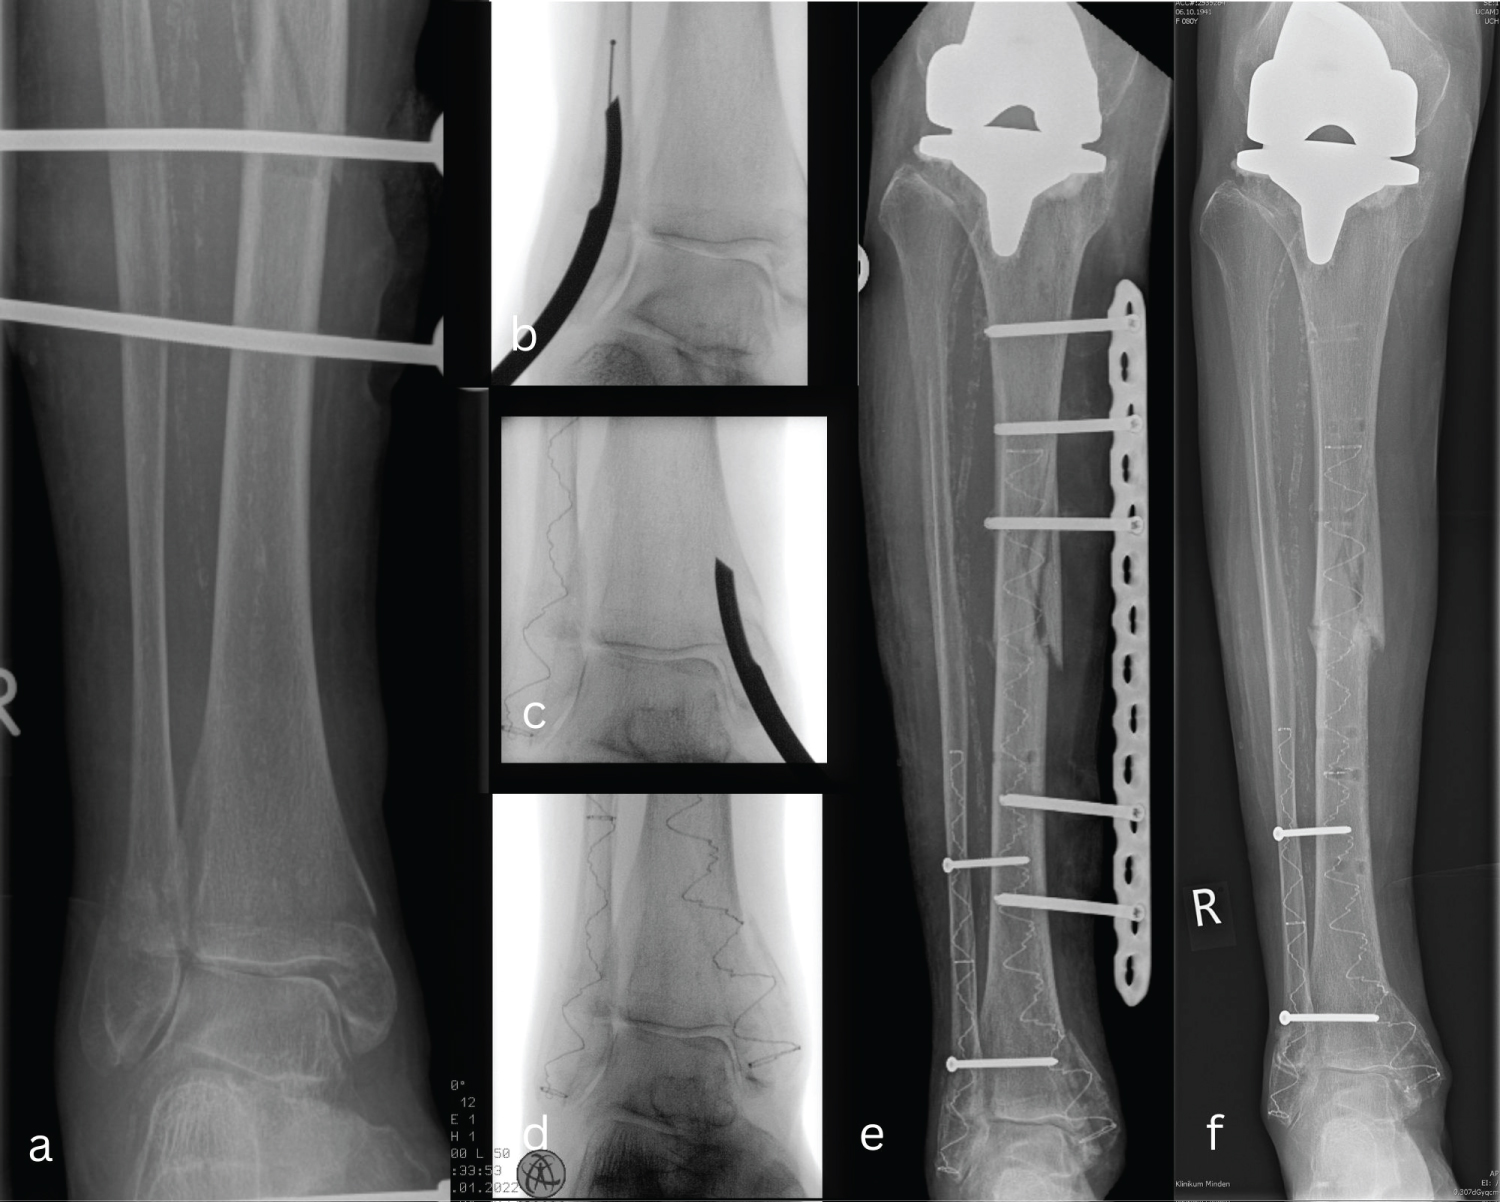

The surgical procedure was performed in the prone position under general anesthesia. The external fixator was first removed, and all Schanz screws were manually extracted given that they were very loose. We started the surgery by stabilizing the fibula. The straight awl was used to locate the optimal entry point at the tip of the fibula under fluoroscopy guidance. After opening the medullary canal, the curved awl was inserted, followed by intramedullary insertion of the elastic wire retrogradely, the position of the wire was controlled with an intraoperative fluoroscopy and the selected balloon catheter of the IlluminOss® system was then inserted. After reduction of the ankle, the balloon was inflated and filled with the monomer, then the curing process was initiated. The balloon was then removed at the bone tip. The intra-operative X-ray showed the correct position of the balloon with correct reduction. Now a second minimal skin incision was made on the tibia distally at the inner ankle tip. Same procedure was repeated with the exception that the intramedullary space was drilled to a size of 8.5, leaving a space for the balloon catheter of the IlluminOss® system to be inserted. To achieve better stability, an angular stable 4.5 Synthes plate was used as a temporary external fixator. The most proximal screw was then placed at the desired position directly under the tibia prosthesis stem, and the screws were inserted proximally and distally over the plate penetrating the IlluminOss® system. Fluoroscopy guidance in both planes shows the correct position of the intramedullary IlluminOss® and the correct position of the bicortical screws at the tibia and fibula. The wound was then closed in a routine fashion (Figure 1 and Figure 2). On the second day of surgery, partial weight bearing of 15-20 kg was started for 6 weeks. After removal of the material, the patient was gradually able to bear full weight. The patient was followed up regularly, after 6 months she reported regaining pre-traumatic mobility.

Figure 1: (a) Peri-implant tibial shaft fracture by coexisting bimalleolar ankle fracture primarily fixed with an external fixator; (b-d) Chronological steps for the minimally invasive technique with the photodynamic bone stabilization system (IlluminOss® system) to stabilize the fibula and tibia; (e) A temporary transverse osteosynthesis with angular stable plate and screws in the form of an external fixator was performed to increase stability; (f) 2 months postoperatively shows a consolidated fracture. View Figure 1